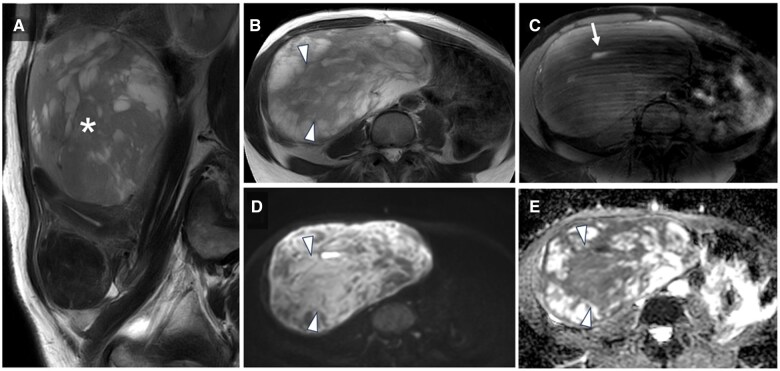

This case report describes a 47-year-old premenopausal woman who presented with abdominal discomfort and had been previously monitored for a suspected uterine leiomyoma. MRI revealed a 15 cm mass within the uterine body and slight intratumoural haemorrhage. One month later, the patient presented with acute abdominal pain and was admitted to the hospital. Contrast-enhanced CT and MRI scans showed significant tumour enlargement to 20 cm, with disruption along the left margin, haemorrhagic ascites, and potential dissemination to the omentum. Total hysterectomy, bilateral salpingo-oophorectomy, and retroperitoneal lymph node dissection revealed uterine leiomyosarcoma with extensive necrosis and rupture. Pathological examination classified the tumour as stage IIB under the International Federation of Gynecology and Obstetrics system, with confirmed omental metastasis. Despite adjuvant chemotherapy, the patient experienced pelvic recurrence 10 months later and died 15 months postoperatively. This case emphasizes the importance of prompt gynaecological intervention for uterine masses exceeding 10 cm, as the risk of rupture increases, particularly when malignancy cannot be excluded based on imaging. Rupture in such cases is associated with a higher risk of recurrence and poor prognosis, making early surgical resection a reasonable consideration. Radiologists should actively communicate these risks to gynaecologists to facilitate timely surgical decision-making and improve patient outcomes.